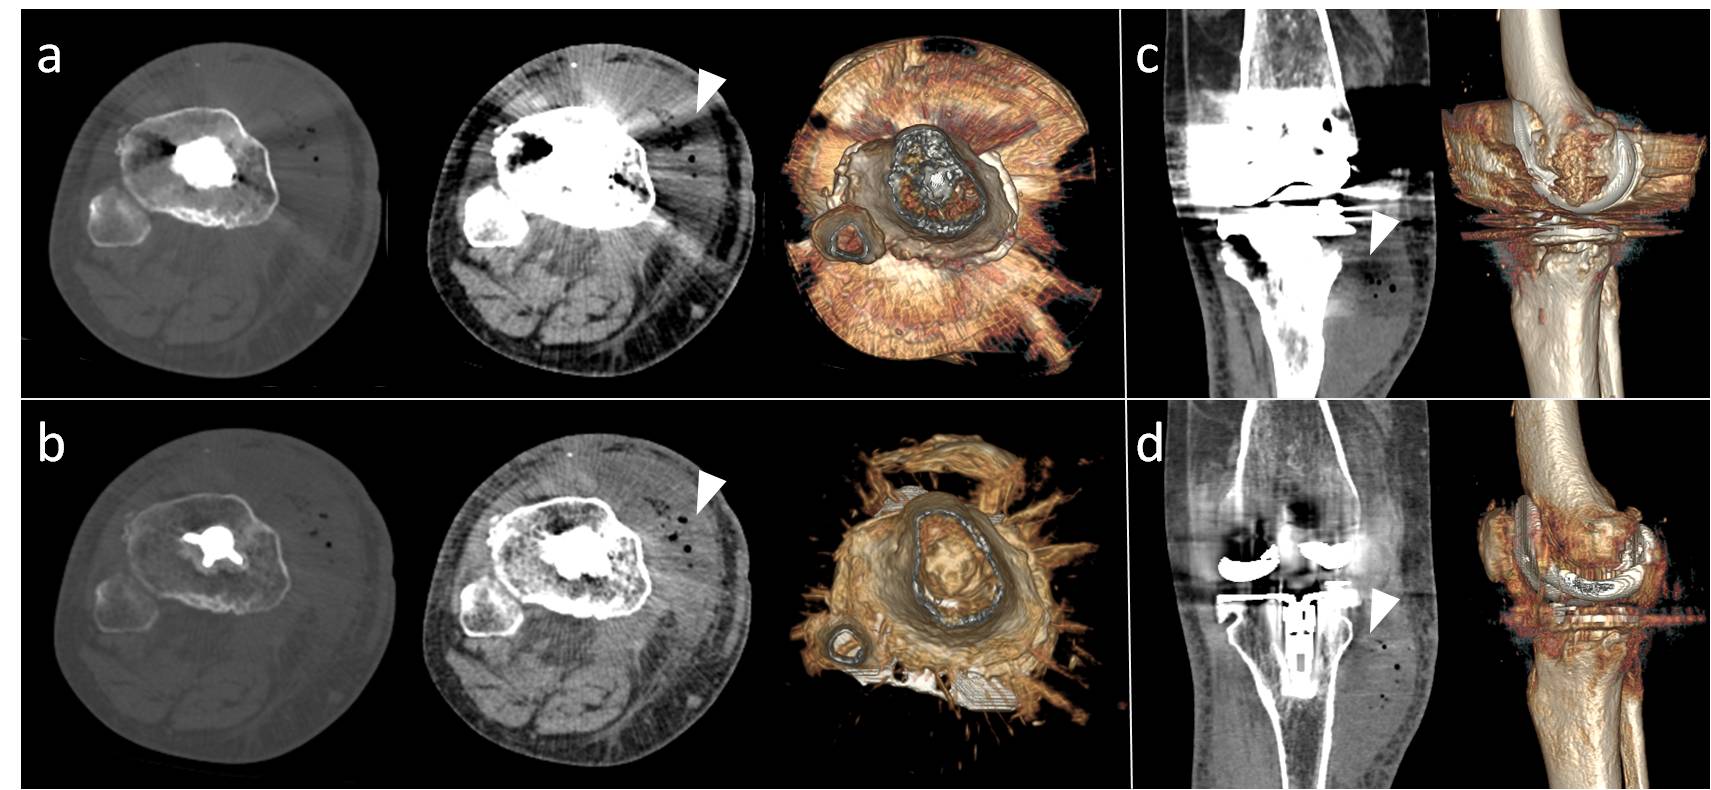

3. Bamberg F, Dierks A, Nikolaou K, Reiser MF, Becker CR, Johnson TR. Metal artifact reduction by dual energy computed tomography using monoenergetic extrapolation. European radiology. 2011;21:1424-1429

4. Pessis E, Campagna R, Sverzut JM, Bach F, Rodallec M, Guerini H, Feydy A, Drape JL. Virtual monochromatic spectral imaging with fast kilovoltage switching: Reduction of metal artifacts at ct. Radiographics : a review publication of the Radiological Society of North America, Inc. 2013;33:573-583

5. Mangold S, Gatidis S, Luz O, Konig B, Schabel C, Bongers MN, Flohr TG, Claussen CD, Thomas C. Single-source dual-energy computed tomography: Use of monoenergetic extrapolation for a reduction of metal artifacts. Investigative radiology. 2014;49:788-793

6. Wang Y, Qian B, Li B, Qin G, Zhou Z, Qiu Y, Sun X, Zhu B. Metal artifacts reduction using monochromatic images from spectral ct: Evaluation of pedicle screws in patients with scoliosis. European journal of radiology. 2013;82:e360-366

14. Lee YH, Park KK, Song HT, Kim S, Suh JS. Metal artefact reduction in gemstone spectral imaging dual-energy ct with and without metal artefact reduction software. European radiology. 2012;22:1331-1340

15. Lewis M, Reid K, Toms AP. Reducing the effects of metal artefact using high kev monoenergetic reconstruction of dual energy ct (dect) in hip replacements. Skeletal radiology. 2013;42:275-282